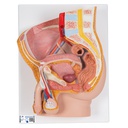

Male pelvis model in median section, 2 part

The male pelvis anatomy model is shown in median section. One half of male genital organs with bladder is shown at the normal position in the male pelvis. The rectum is removable for a more detailed study of the male pelvic anatomy. This high quality anatomy model is delivered on baseboard offering the possibility to be mounted to the wall.